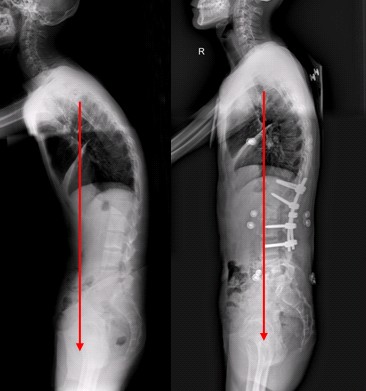

1、病情控制的较好的患者会出现驼背,脊椎变形的现象。严重的病情症状会导致大小便失禁,劳动力丧失。对社会和家庭造成影响。

4、肺部病变:得了该疾病胸廓会发生改变,导致肺部病变,严重者在x片中会发现有空洞。患者常常会伴随呼吸困难,由于胸廓受到抵压,或导致胸廓局部难受。